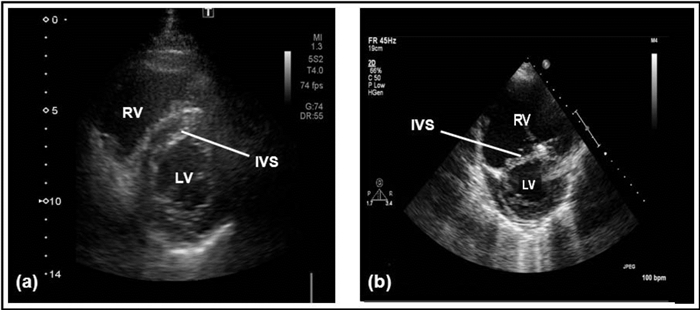

超声心动图通过不同切面显示右心室长轴、左心室短轴和四腔心层面显示右心的结构特点,见图 3。[8]

| 图 3 右心室长轴可以显示右心房、右心室及右心室流出道;左心室短轴显示右心室呈新月形及部分三尖瓣瓣叶;心尖四腔心显示左右心房、左右心室及三尖瓣 |